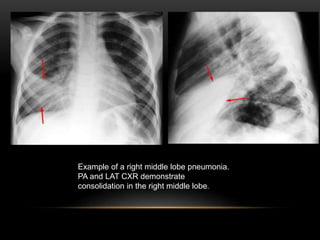

Example of a right middle lobe pneumonia.

PA and LAT CXR demonstrate

consolidation in the right middle lobe.